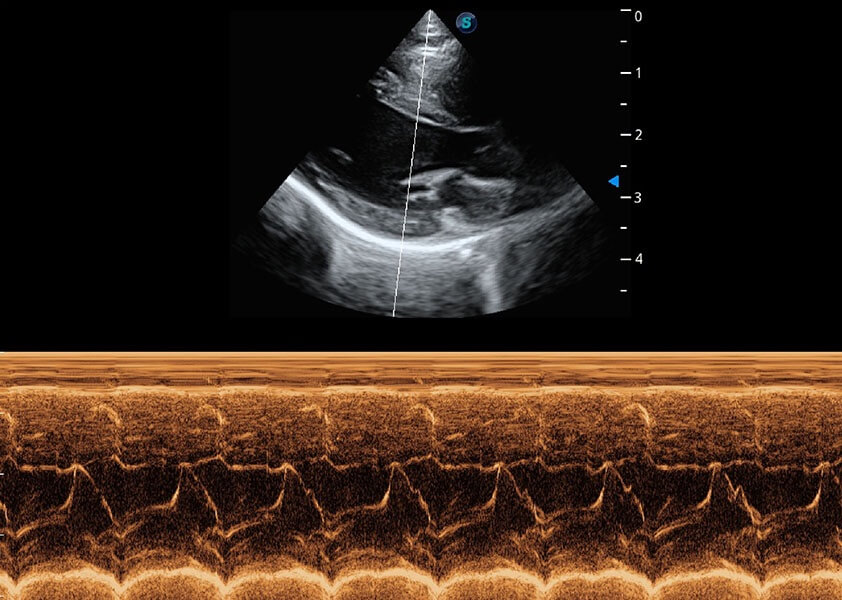

ProPet 60 作為一款高端臺(tái)式動(dòng)物超聲設(shè)備,為動(dòng)物醫(yī)生的日常診斷提供了一系列貼合動(dòng)物臨床需求、解決臨床實(shí)際問題的高級成像功能。憑借全系列高清探頭,滿足醫(yī)生對腹部、心臟、生殖、淺表、肌骨等成像的所有需求,切實(shí)幫助您提升檢查效率,提高診斷信心。

獸用彩色多普勒超聲診斷系統(tǒng)